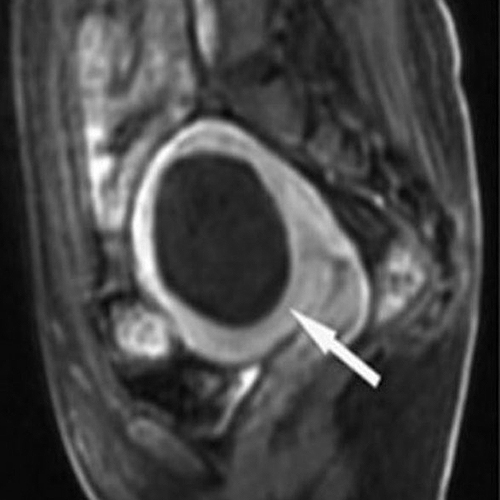

Зөв дүгнэлт гаргахын тулд MRI зэрэг нарийн шинжилгээ хийлгэх шаардлагатай.

9см том миома оношлогдсон

Тринитид ирж

Өндөр давтамжит эмчилгээ хийсэн

Эмчилгээс хойш 10 сарын дараа

2см болж хэмжээ 77% багассан